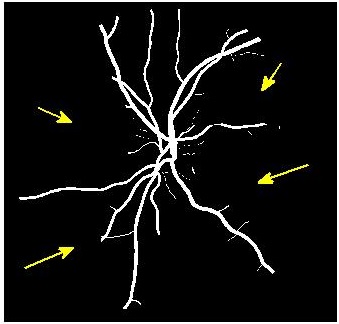

Figure 4 (a) shows an example retinal image followed by its ground truth manual segmentation in Figure 4 (b). Figure 4 (c) shows segmentation result for scaling factor when using the original HR images to train the U-Net followed by the results when trained on the super resolved images generated by , (Figure 4 (d)), (Figure 4 (e)), (Figure 4 (f)), SR-RF (Figure 4 (g)), SSR (Figure 4 (h)) and (Figure 4 (i)). Obviously the results from provide results most similar to those of HR images. This is also validated by the quantitative results in Table 3. The areas where different methods are unable to obtain accurate segmentation are highlighted by yellow arrows. Due to poor quality of super resolved images most of the methods do not segment the finer vasculature structures, while SSR and SR-RF are unable to segment some of the major arteries. Importantly, our method performs much better than the low resolution image () which performs poorly due to low resolution.

![]() |

| (a) | (b) | (c) | (d) | (e) |

| (f) | (g) | (h) | (i) | (j) |